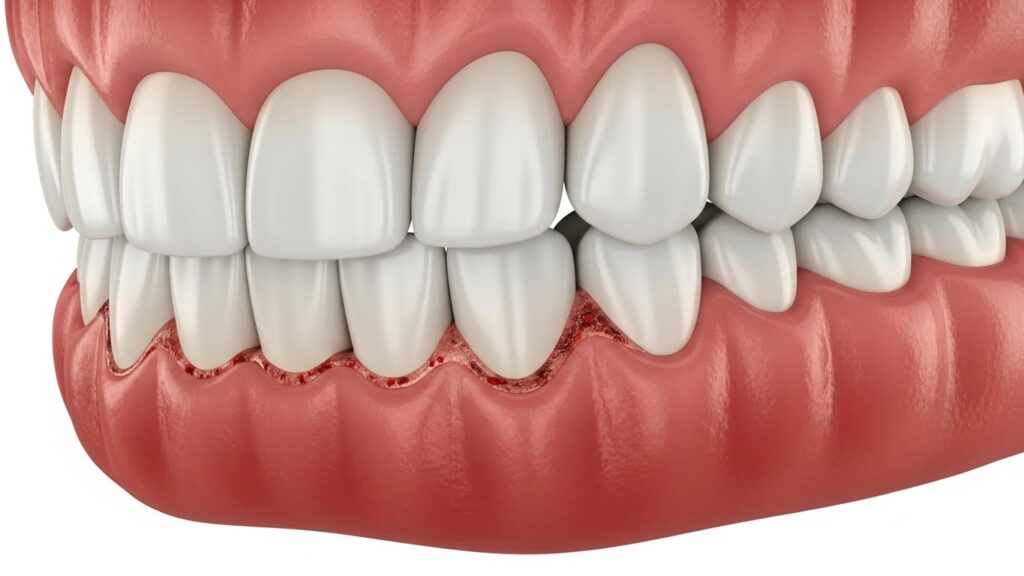

Bleeding gums allow harmful bacteria to slip past the gumline - What happens next is what shocks most people

As inflammation builds, gum fibers weaken and begin to pull back — it’s only the first visible sign of something deeper happening inside your mouth.

ONGOING INFLAMATION

Redness, swelling, sensitivity, and stronger bleeding episodes start showing up. Breath worsens fast — even after brushing.

The problem is now growing beneath the surface.